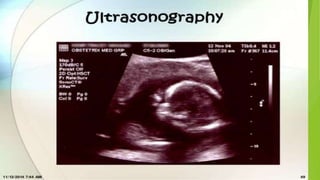

Ultrasonography

 The production of high frequency sound waves which are reflected or echoed

when beamed into the body and an interface is encountered between

different types of tissues or structures with different densities.

 These echoes can be translated into visible images of the tissues or structures

encountered.

Uses of ultrasonography